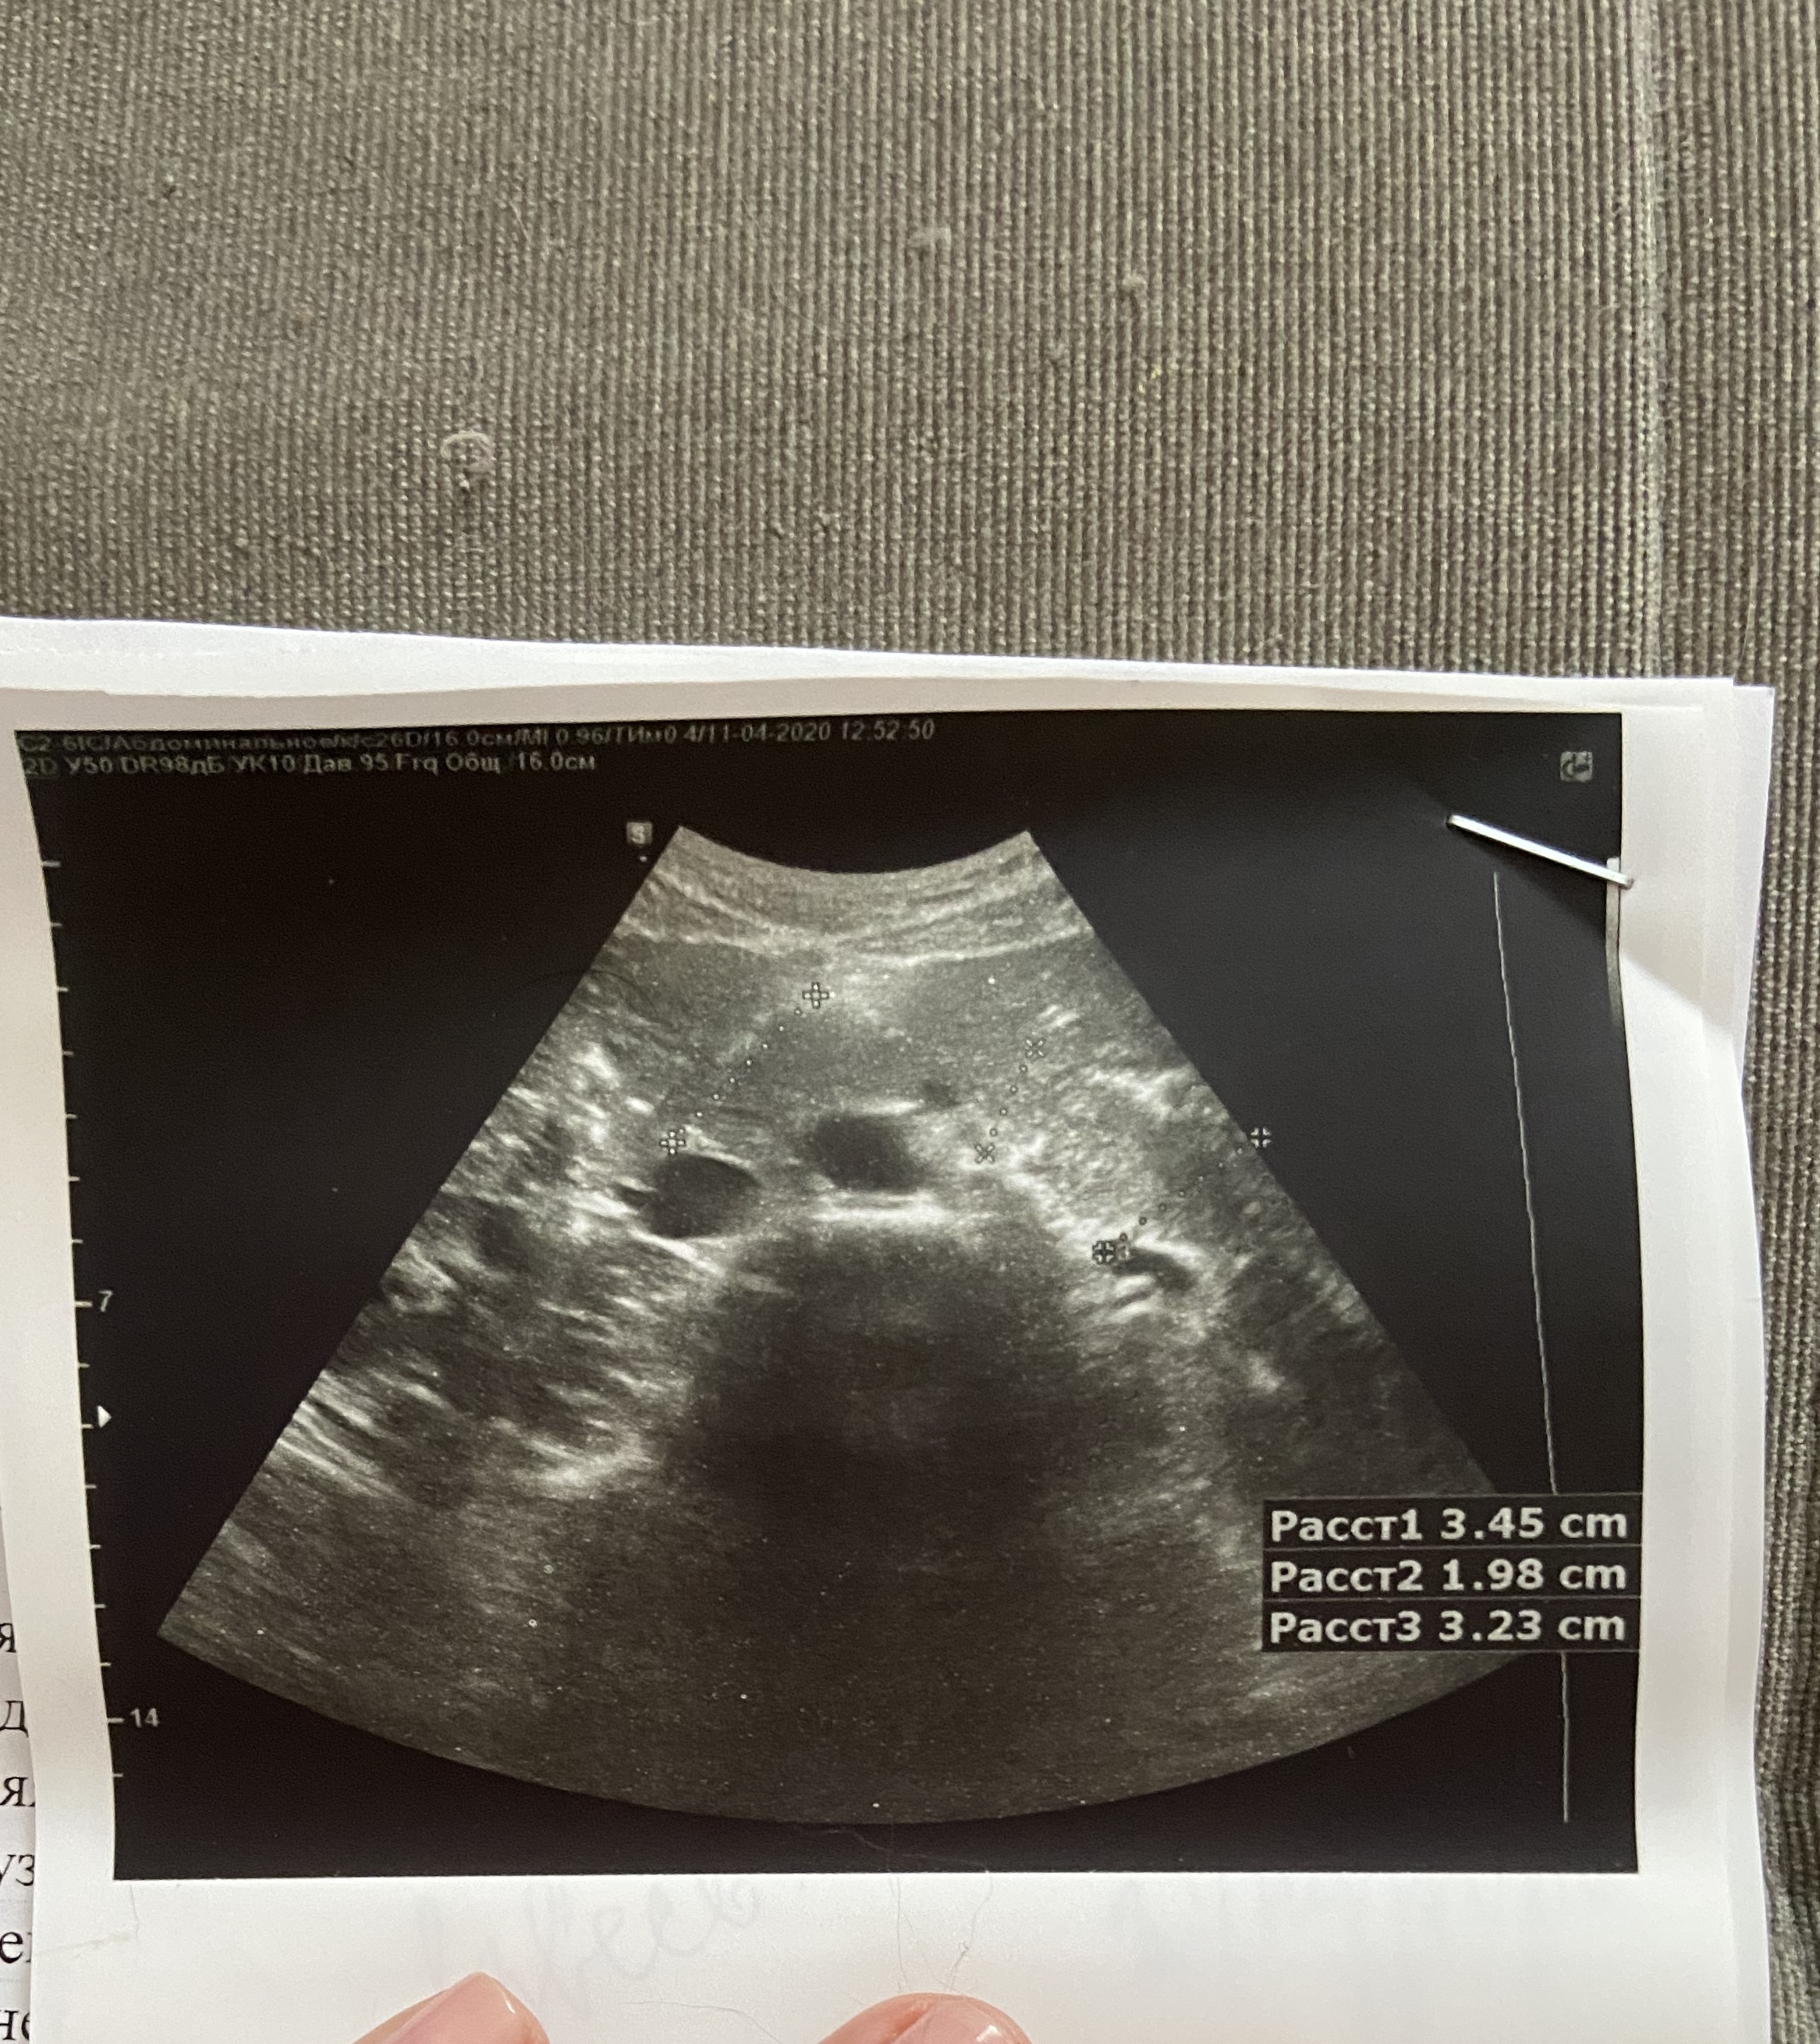

Завтра прикреплю узи.Нашла у себя сосудистые звездочки и мне очень страшно

Спасибо Всем большое,так приятна эта поддержка)))Не смогла ещё разобраться,как отвечать на личные сообщения,сейчас буду смотреть и выкладывать узи...Посмотрите ,пожалуйста

Хочу поскорее начать лечение и заказать препараты))Как считаете по результатам узи ,можно заказывать соф+вел,без рибавирина или дождаться анализов крови?

По результатам УЗИ нет ничего критичного. Диффузные изменения поджелудочной и хронический холецистит частые спутники гепатитчиков. Хорошо, что камней в желчном нет. Для улучшения самочувствия можно обойтись регулировкой режима питания, исключением продуктов, вредных для желчного, приёмом желчегонных препаратов.